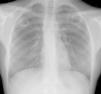

We report the case of a 24-year-old Caucasian woman, smoker (5 cigarettes a day), with no significant medical history, and a journalist by profession. She presented with a 3-month history of purulent expectoration which did not resolve after various courses of antibiotics. She had no other associated symptoms. She reported work-related contact in London, 20 months previously, with an individual infected with tuberculosis (TB), and also sporadic contact with a friend with a diagnosis of TB. No contact tracing was performed in either case. In view of the persistent symptoms, a chest radiograph was requested, which revealed 2 practically symmetric and well-defined cavitating lesions in both upper lobes (Fig. 1). Auramine staining was positive and Mycobacterium tuberculosis was isolated from the culture. Serology was negative for hepatotropic viruses and human immunodeficiency virus.

There is no specific diagnostic sign or radiographic pattern for TB. The radiological spectrum is wide, but it is clear that some very suggestive patterns can be recognized, for example, cavities in the upper lobes. In most cases, these cavities are multifocal, with thick irregular walls.1,2 In contrast, our case presented with 2 isolated, bilateral, well-defined cavities, a most curious presentation.